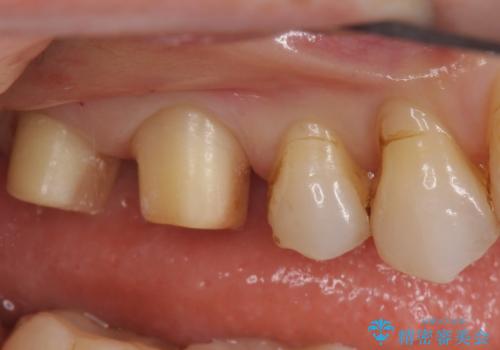

- 銀歯を白くしたいとのことで来院されました。

銀の詰め物を除去した後、その奥にある古い詰め物も除去し完全にむし歯を取り切ったことを確認してからセラミッククラウンを装着していきます。

詰め物の除去後、残った歯が薄い場合は今後の破折リスクを考慮して被せ物での修復処置を提案することがあります。